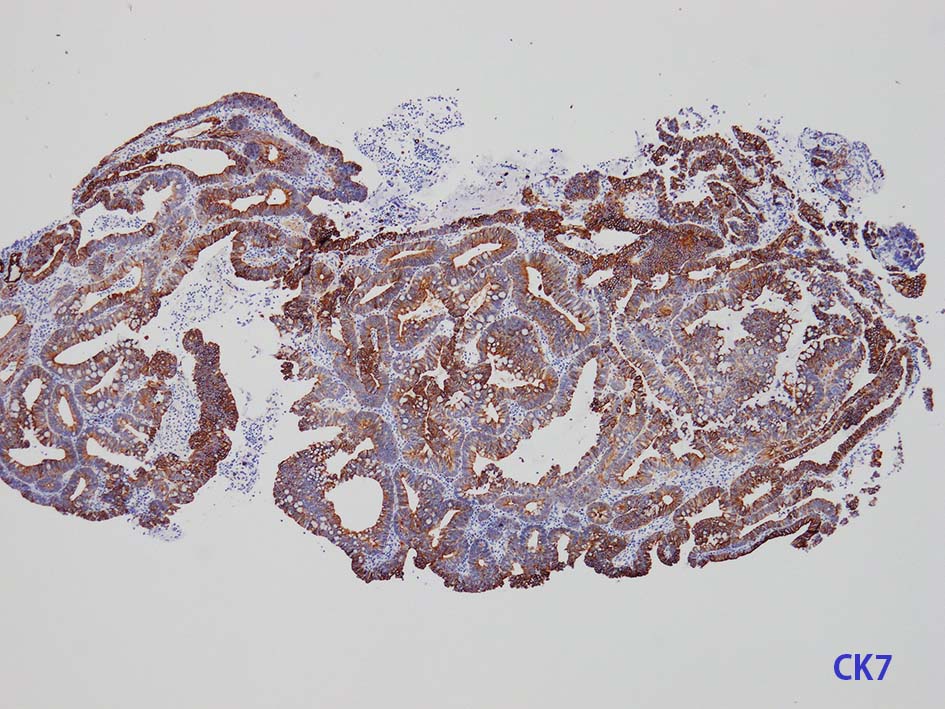

膀胱原発腺癌の診断に, サイトケラチン7および20、34βE12、トロンボモジュリン、CDX2およびβカテニンなどの免疫組織化学的パネルが提案されている。しかし他の原発部位に発生する腺癌と組織像だけでなく免疫組織化学的特徴が重複している. 原発性腺癌と転移性腺癌では予後や治療法が大きく異なるため, 鑑別診断において膀胱腺癌の診断を下す際には、臨床的、画像的、組織的、および免疫組織化学的な相関を注意深く確認する必要がある。

腸管型の腺癌。大腸の高分化腺癌と組織学的に区別は難しい.

neutrophilic exudate の付着する腸管型腺癌部分. 核はより腫大し円形、vesicularとなっている. 上記腸管型とはCK20, CK7のそまりが異なっていた. 変性のためかもしれない.

mark-g.gif 免疫染色

GI tract, とくに大腸癌の膀胱浸潤/転移を最初に考えた.